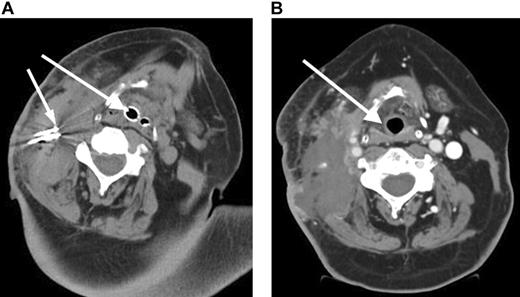

A 57-year-old male presented with stage I follicular center cell lymphoma. He received CHOP with rituximab followed by 3000 cGy radiation with complete resolution of the neck mass. A relapse occurred 2 months later, and a fine-needle aspiration revealed a histologic transformation of his disease in the neck. He received an additional cycle of CHOP followed by ICE (ifosfamide, carboplatin, etoposide) chemotherapy and an additional 3600 cGy to the neck.6 He then received a reduced-intensity allogeneic stem cell transplant.7 However, he later developed progressive neck pain and a rapidly enlarging neck mass (Figure 1A). Due to impending airway obstruction, maximum prior radiation, and the patient's refusal to undergo a tracheostomy, RF ablation combined with liposomal doxorubicin to increase tissue coagulation and intratumoral drug accumulation was performed at 4 different locations in the right neck without complication.8 Because of the location of the mass and the potential for worsening airway obstruction, the patient was observed in the intensive care unit following the RF ablation. Subsequently, the patient achieved resolution of his symptoms (Figure 1B) but died 5 weeks later from his disease progression at other sites.

Rapidly enlarging large B-cell lymphoma neck mass causing airway obstruction. (A) Pre-RF ablation CT scan shows a large right cervical mass with extensive tracheal deviation with compressed airway expanded by endotracheal tube (large arrow) and RF ablation needles (small arrow) within cervical mass. (B) Post-RF ablation CT demonstrates a devascularization and reduction in cervical mass and improvement of tracheal deviation with shift of trachea (arrow) to midline.